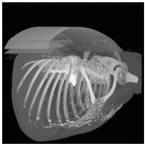

3.6. Post-Processing: 3D Projection

To generate a 3D projection from the 2D output, a post-processing step is required. This step involves aggregating the CT image slices and transforming them into a coherent 3D representation. In this process, the Mayavi [59] library in Python serves as a valuable tool for facilitating the conversion of the 2D model output into a 3D representation.

The process begins by obtaining segmentation masks for each individual slice of the CT-scan. These masks provide information about the different regions within the lung. Next, the segmented slices are merged to create a unified representation. This merging process involves swapping the axes of the segmented data, ensuring that the resulting 3D projection can be visualized as a cohesive volume.

The utilization of the Mayavi library streamlines the transition of the 2D model output to a 3D representation. This library offers robust functionality for transforming and displaying the segmented data in a three-dimensional space. By employing Mayavi, the proposed approach enhances diagnostic capabilities, providing clinicians with a comprehensive 3D visualization of lung structures and infection areas.